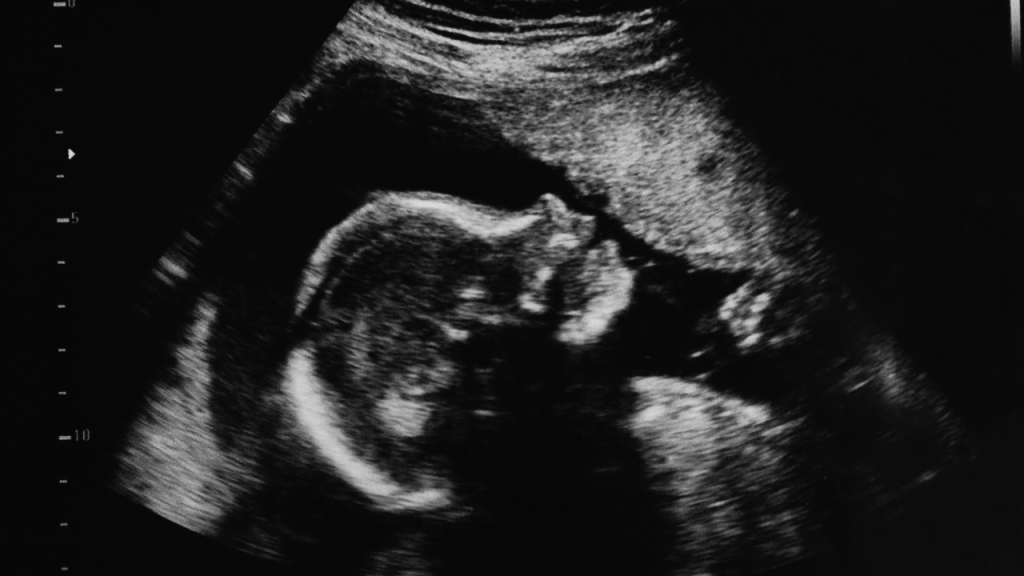

Un tratamiento pionero administrado antes del nacimiento ha marcado un hito en la medicina moderna. Una niña con riesgo de padecer atrofia muscular espinal —un trastorno genético grave— fue tratada en el útero y, a sus dos años de vida, no presenta signos de la condición. Este caso fue publicado recientemente en el New England Journal of Medicine.

Este hito médico se logró gracias a la colaboración entre científicos del Hospital de Investigación Infantil St. Jude y una familia que ya había enfrentado la enfermedad. Tras perder a un hijo por AME tipo 1, los padres se sometieron a pruebas genéticas que confirmaron que su próxima hija también la padecería. Fue entonces cuando propusieron, junto con los médicos, una idea audaz: administrar risdiplam antes del nacimiento.

Risdiplam es un tratamiento oral aprobado por la FDA para casos de AME. Actúa ayudando al cuerpo a producir más proteína SMN, esencial para la salud muscular. En este caso, se suministró a la madre durante las últimas seis semanas del embarazo. Los médicos querían evaluar tres aspectos clave: si era posible administrarlo con seguridad, si la madre lo toleraba bien y si podría beneficiar a la bebé en desarrollo. La intervención fue todo un éxito.

Tras el parto, se confirmó que la niña presentaba algunas anomalías prenatales, pero ninguna relacionada con la exposición al medicamento. Comenzó a tomar risdiplam una semana después de nacer y, hoy, a los dos años, no muestra signos de la enfermedad.